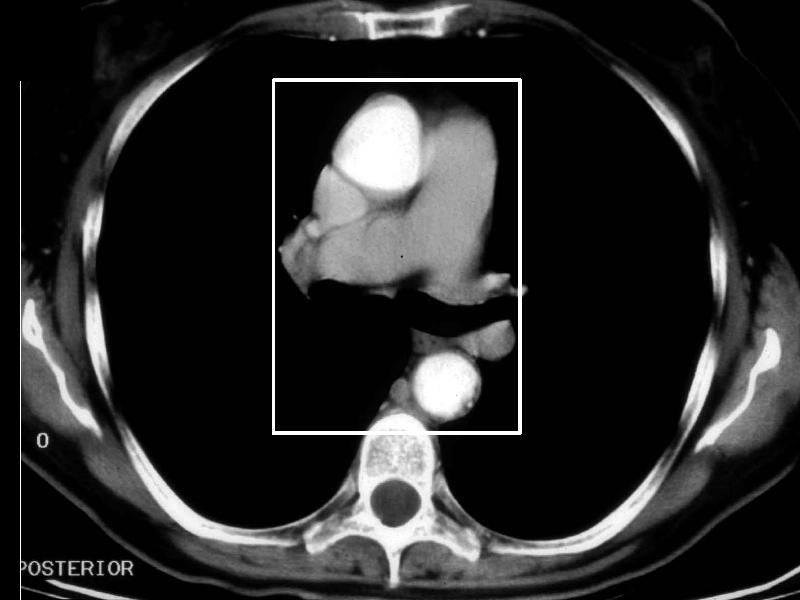

MS 156 CT 63